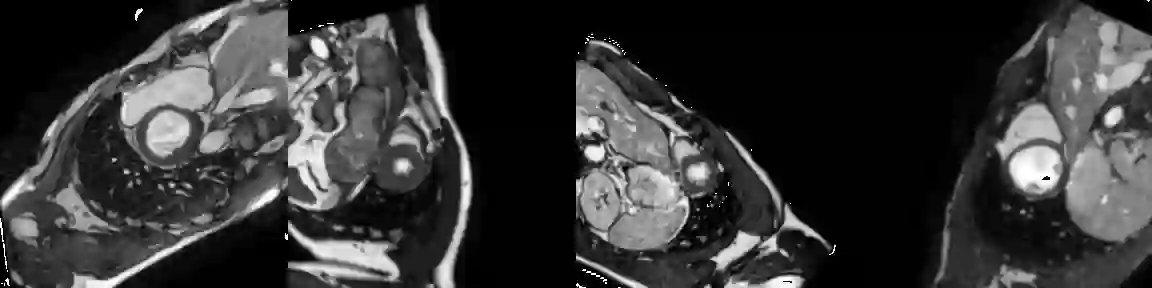

Training medical image segmentation models usually requires a large amount of labeled data. By contrast, humans can quickly learn to accurately recognise anatomy of interest from medical (e.g. MRI and CT) images with some limited guidance. Such recognition ability can easily generalise to new images from different clinical centres. This rapid and generalisable learning ability is mostly due to the compositional structure of image patterns in the human brain, which is less incorporated in medical image segmentation. In this paper, we model the compositional components (i.e. patterns) of human anatomy as learnable von-Mises-Fisher (vMF) kernels, which are robust to images collected from different domains (e.g. clinical centres). The image features can be decomposed to (or composed by) the components with the composing operations, i.e. the vMF likelihoods. The vMF likelihoods tell how likely each anatomical part is at each position of the image. Hence, the segmentation mask can be predicted based on the vMF likelihoods. Moreover, with a reconstruction module, unlabeled data can also be used to learn the vMF kernels and likelihoods by recombining them to reconstruct the input image. Extensive experiments show that the proposed vMFNet achieves improved generalisation performance on two benchmarks, especially when annotations are limited. Code is publicly available at: https://github.com/vios-s/vMFNet.